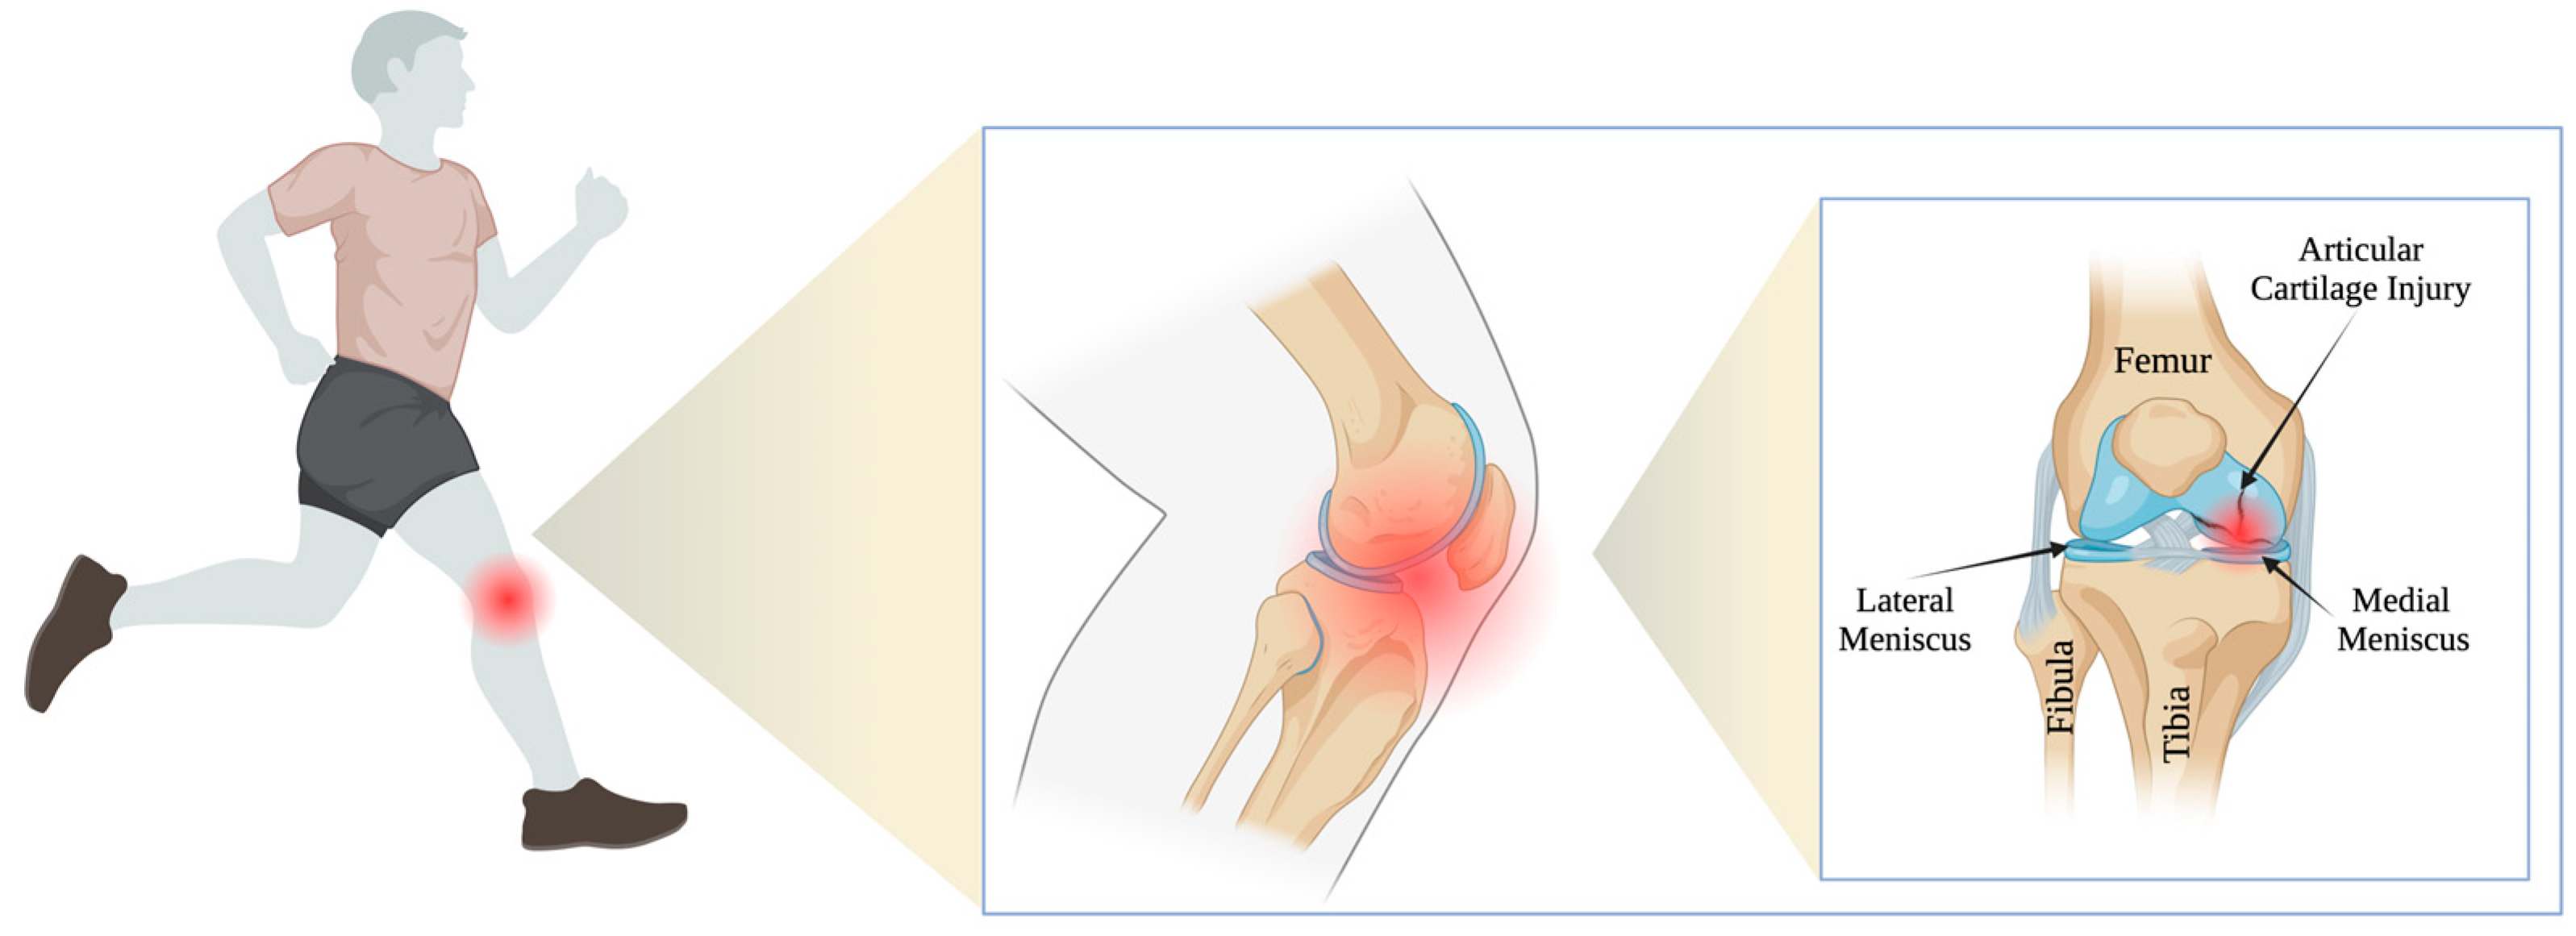

1. Introduction

2.2. Operation Procedure